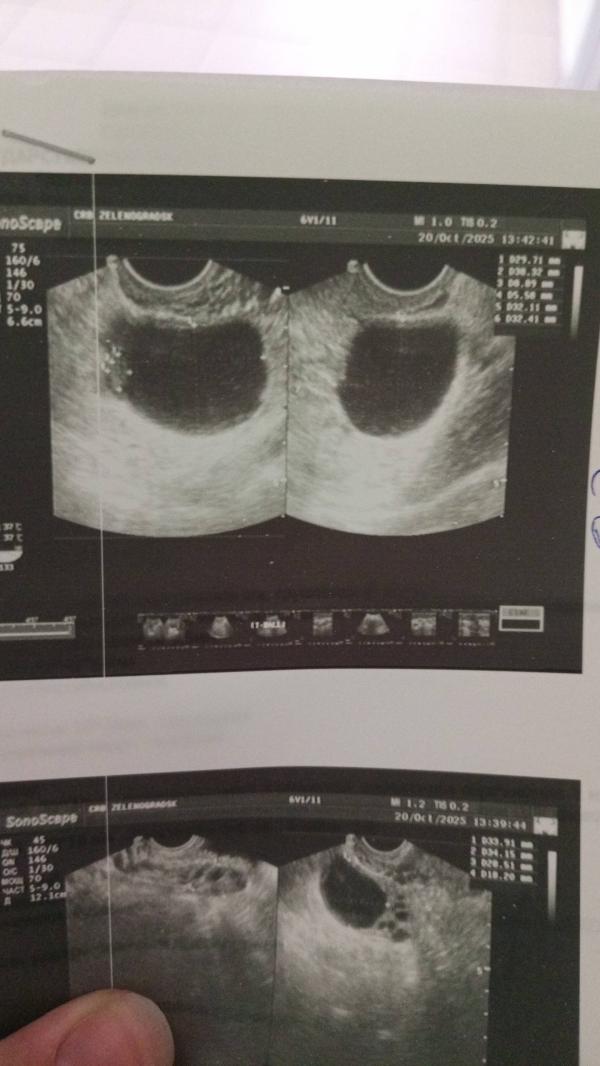

Узи сделала, киста есть...

Сама не рассосётся, через 3 месяца повторое узи, если растёт, то операция 🥺 если нет, то наблюдаем... При сильных болях вызывать скорую и в больницу. Откуда взялась понять не могу, но сказали из-за гормонального сбоя могла появиться, беременность и тд. Никогда не думала что столкнусь с такой проблемой.

Находится в яичнике и внутри есть какое то содержимое, а еще нарост... Размер около 4 см